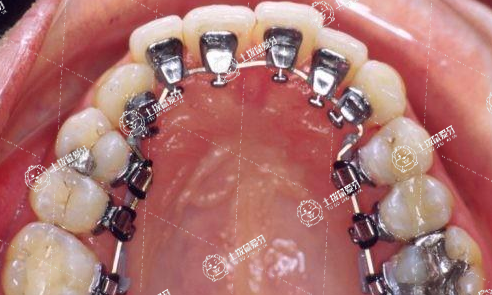

舌側(cè)矯正是一種將矯治器粘接于牙齒舌側(cè)上進(jìn)行牙齒矯正治療的正畸技術(shù)。舌側(cè)矯正從外觀上看不到任何的正畸治療裝置,不僅能有效的避免成年人進(jìn)行牙齒矯正時(shí)成為“鋼牙妹”的尷尬,而且還能達(dá)到比唇側(cè)矯正更精確的矯正效果,是真正意義上的“隱形矯正”技術(shù)。舌側(cè)矯正技術(shù)一經(jīng)問世,就受到了演員、律師、教師等美觀或職業(yè)要求較高患者的廣大歡迎,也是目前牙齒矯正領(lǐng)域中最為高端、復(fù)雜的矯正技術(shù)。

舌側(cè)正畸的矯治器全部安裝于牙齒的舌側(cè)面進(jìn)行正畸治療,因此旁人無法看見托槽鋼絲,可以做到完全隱形,讓牙齒悄然排列整齊。